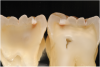

Next, regardless of chalkiness, the clinician examines the dry grooves for the presence of any areas of localized enamel breakdown, or microcavitations, which represents ICDAS code 3 lesions (Figure 12 and Figure 13). Additionally, the presence of an underlying shadow, which indicates dentin caries showing through, is considered an ICDAS code 4 lesion (Figure 14). Either or both of these findings results in a classification of the tooth structure as CCS code 2 moderate.

Fig 12. ICDAS code 3: Area of localized enamel breakdown (microcavitation) indicated.

Figure 12

Fig 13. ICDAS code 3: Section showing penetration of caries into middle third of dentin.

Figure 13

Fig 14. ICDAS code 4: Dark gray shadow visible in dentin in indicated area.

Figure 14